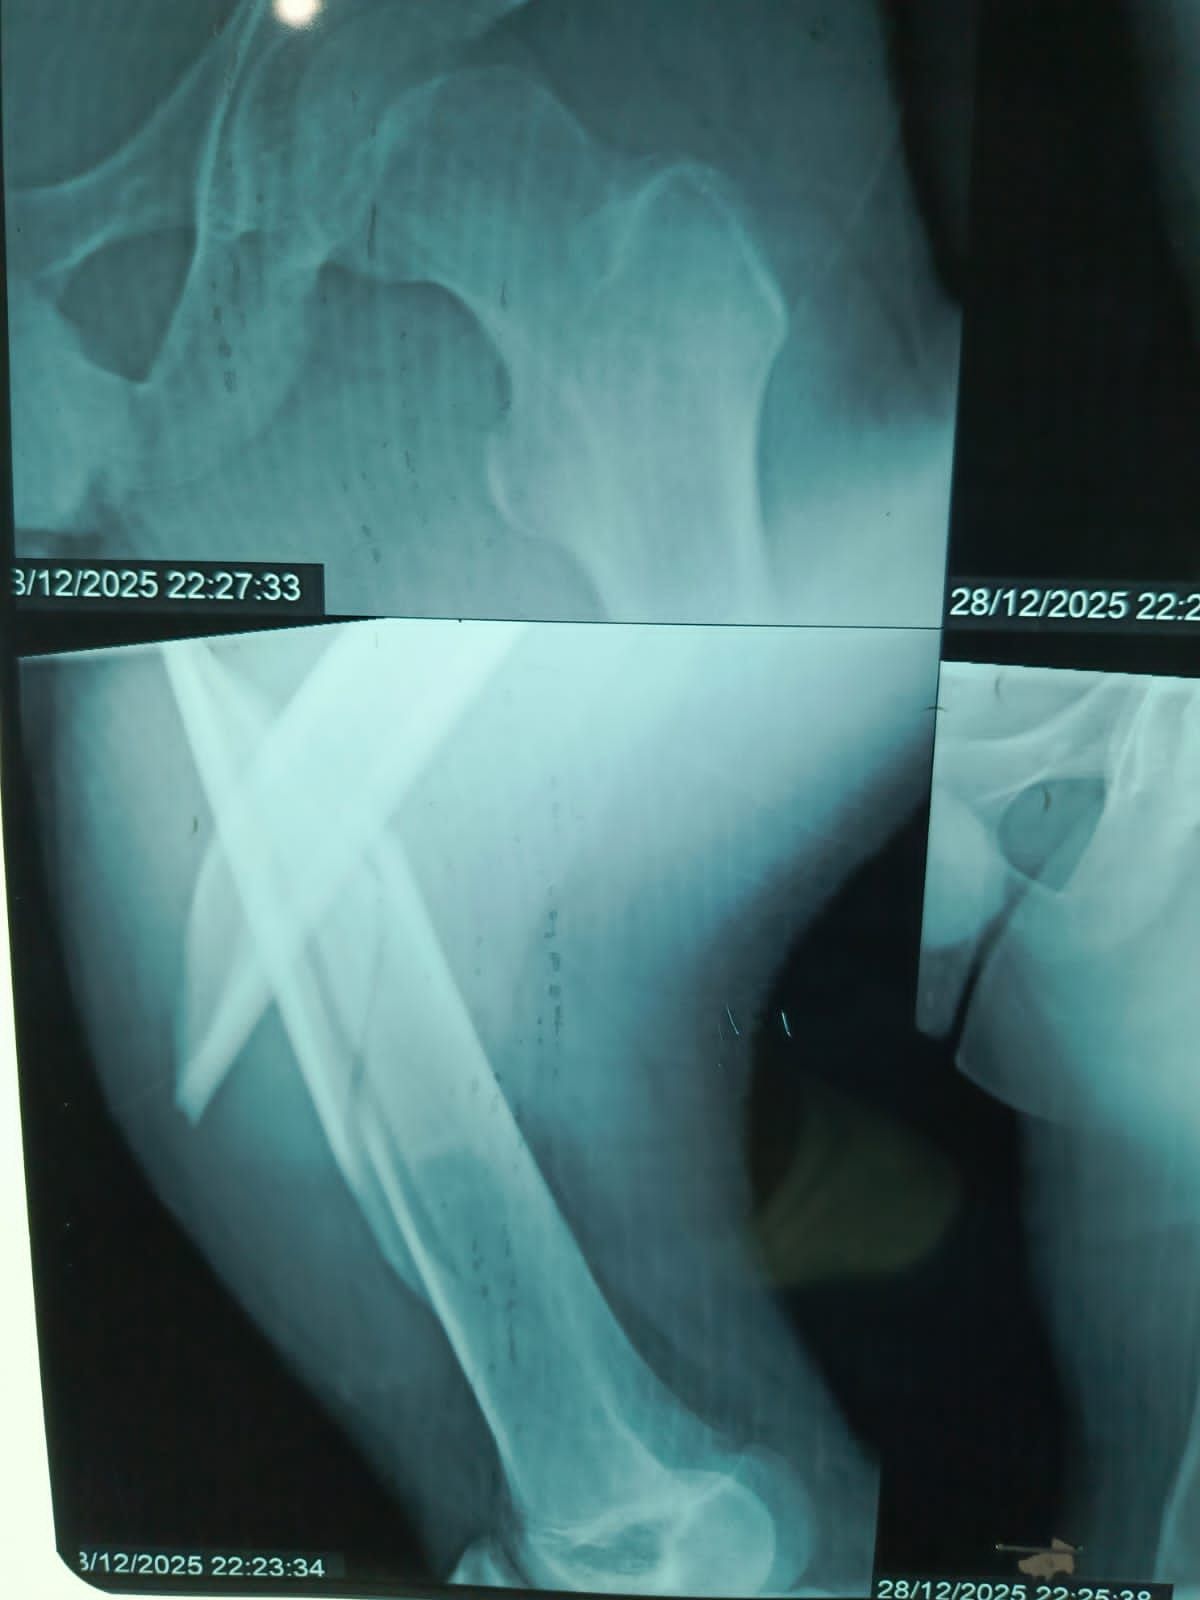

نجح الفريق الطبي بقسم الطوارئ والعمليات بمستشفى مغاغة العام بمحافظة المنيا ، في إنقاذ شاب يبلغ من العمر 16 عامًا، تعرض لحادث مروري مروع أسفر عن كسر مفتت متعدد المواضع بعظمة الفخذ الأيسر، وذلك من خلال إجراء جراحة متقدمة باستخدام تقنية المسمار النخاعي التشابكي في زمن قياسي.

وفور وصول المصاب إلى قسم الطوارئ، جرى التعامل الفوري معه، وتم اتخاذ القرار الطبي العاجل بإجراء جراحة المسمار النخاعي التشابكي دون فتح موضع الكسر، بما يتوافق مع أحدث البروتوكولات الطبية العالمية. واستغرقت العملية نحو ساعتين ونصف فقط، غادر بعدها المريض غرفة العمليات في حالة مستقرة.

وتميزت الجراحة بعدة مزايا، من بينها : جروح جراحية محدودة للغاية ، وتقليل فرص النزيف والعدوى إلى أدنى حد ، وتسريع معدلات التئام العظام مقارنة بالطرق التقليدية.